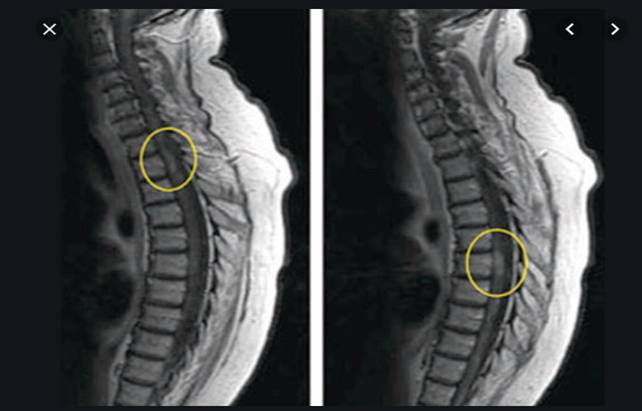

Trường hợp thứ tư: Một phụ nữ 30 tuổi có triệu chứng đau bên đùi trái trong khi cô ta tham gia vào một cuoc chay đua Eco-Challenge 2000 ở Borneo, xuất hiện một nốt, cục kích thước 4x3cm ở vùng đùi trái đã góp phần làm đau xé cơ của bệnh nhân; cục này tồn tại 12 tháng và sau đó cô ta phải nhập viện bệnh viện nhiệt đới London. Chụp cộng hưởng từ (MRI) ở đùi cho thấy một tổn thương phân thùy (lobulated lesion) bên trong bó cơ lớn, xung quanh có phù. Kết quả chẩn đoán huyết thanh học với Gnathostoma dương tính. Điều trị liệu trình 21 ngày bằng albendazole cho thấy có giảm dần kích thước tổn thương nhưng không hết hẳn hoàn toàn.